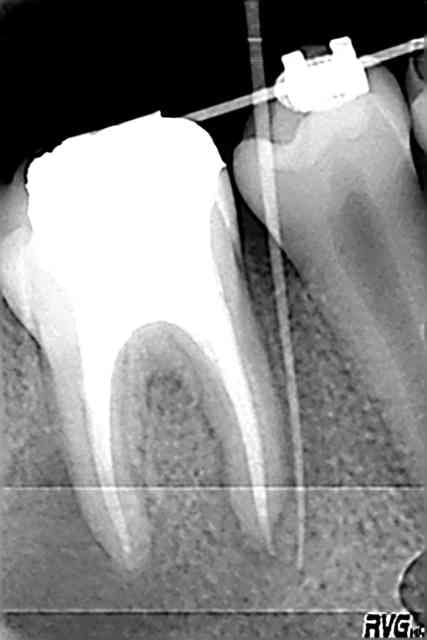

Je fais l'endo la semaine suivante, je suis pas trop mécontent de l'aspect final (image 02, celle de droite).

J'obture 5 jours apres en coronaire avec un bon vieil amalgame des familles et la voilà qui part chez l'ortho pour la pose de ces affreuses brackets.